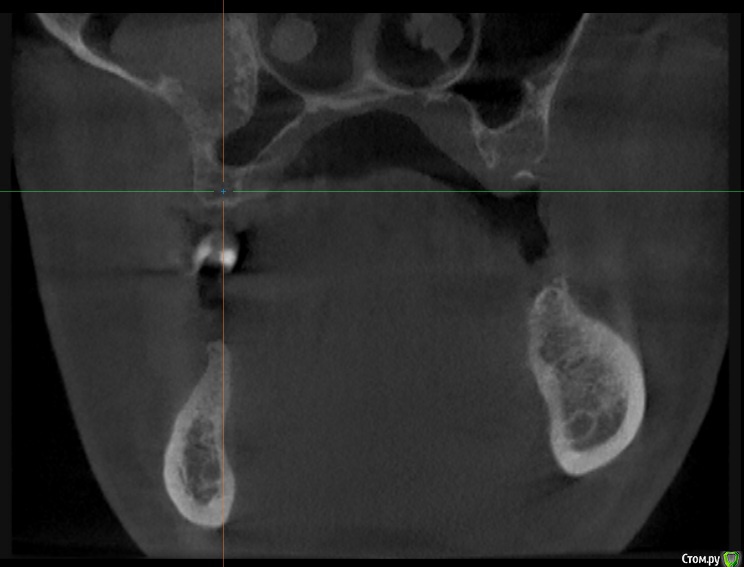

alboard Опубликовано 9 марта, 2017 Поделиться Опубликовано 9 марта, 2017 В области 16,17,18 дно отсутствует. Какая здесь может быть тактика? Ссылка на комментарий

alboard Опубликовано 9 марта, 2017 Автор Поделиться Опубликовано 9 марта, 2017 Еще парочка Ссылка на комментарий

Dok22 Опубликовано 9 марта, 2017 Поделиться Опубликовано 9 марта, 2017 В пазухе какое то образование. 1 Ссылка на комментарий

mr.Fog Опубликовано 9 марта, 2017 Поделиться Опубликовано 9 марта, 2017 Скорее всего это кальцифицированные останки радикулярной кисты. Ссылка на комментарий

Oscar Опубликовано 9 марта, 2017 Поделиться Опубликовано 9 марта, 2017 давно зубы удалены? Похоже на ретенционную кисту пазухи... Можно попробовать отслоить шнайдер снизу, если перфорация выход только "парашют"... Ссылка на комментарий

drpetrovich Опубликовано 13 марта, 2017 Поделиться Опубликовано 13 марта, 2017 Действительно по томограмме больше похоже на резидуальную кисту, т.е. при зондировании проваливаешься не в пазуху, а в полость кисты. Отделяемое было кстати? Вопрос про давность удаления актуален. Ссылка на комментарий